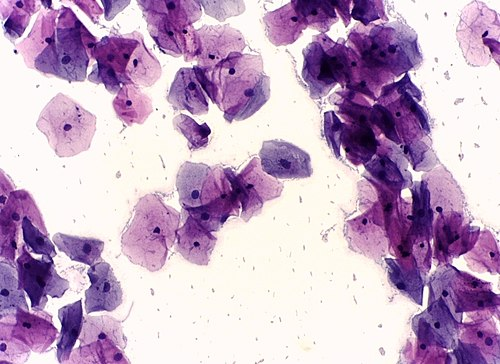

Urinalysis Sediment

Centrifuged urine sediment showing casts, crystals, and cells